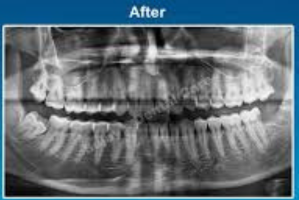

Tooth Extractions involve the removal of a tooth that is damaged, infected, or causing crowding. Impaction treatment refers to removing teeth (commonly wisdom teeth) that fail to erupt properly and cause pain or infections. Both procedures are done under anesthesia for comfort and safety.

Before & After Care